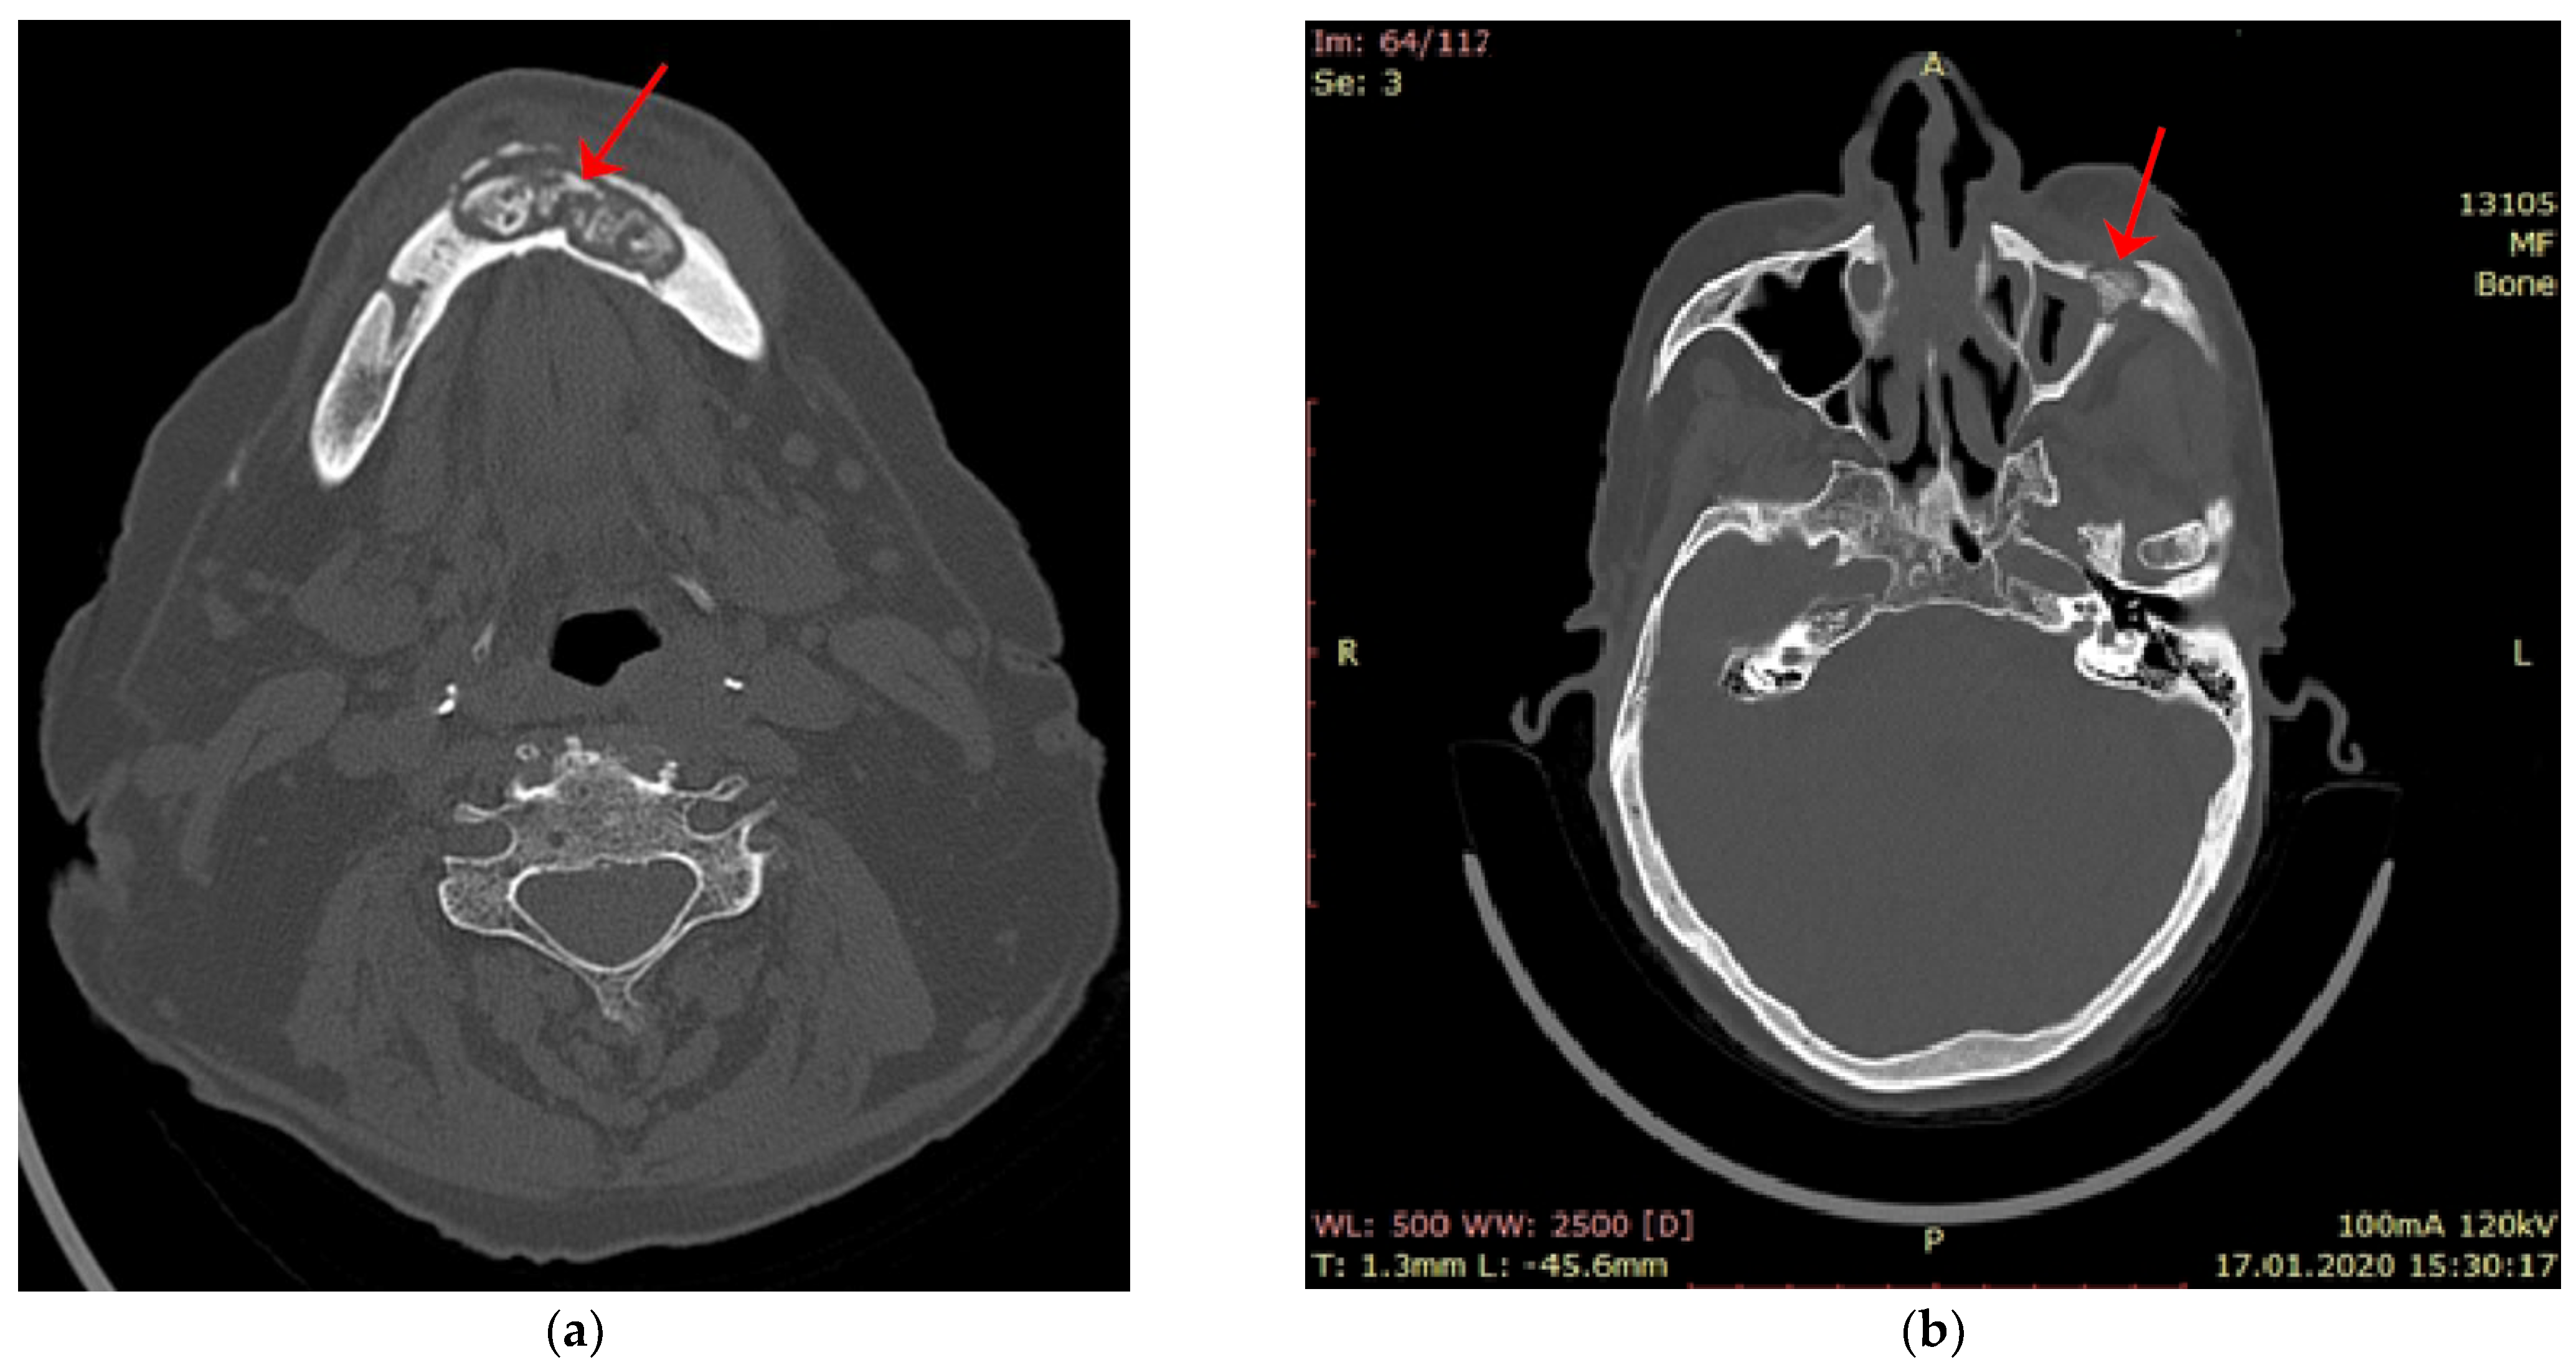

- Baba, A.; Goto, T.K.; Ojiri, H.; Takagiwa, M.; Hiraga, C.; Okamura, M.; Hasegawa, S.; Okuyama, Y.; Ogino, N.; Yamauchi, H.; et al. CT imaging features of antiresorptive agent-related osteonecrosis of the jaw/medication-related osteonecrosis of the jaw. Dentomaxillofac. Radiol. 2018, 47, 20170323. [Google Scholar] [CrossRef] [PubMed]